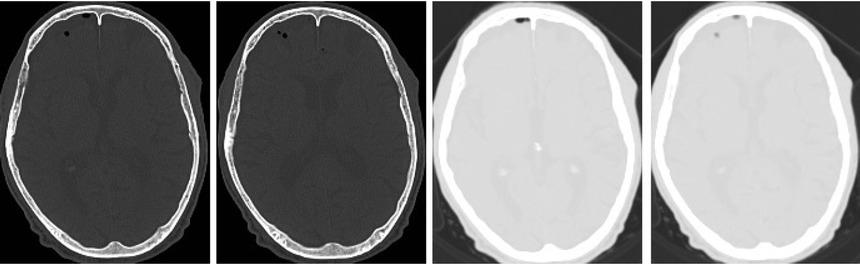

A second head CT scan was performed on the second postoperative day, five hours after the end of the hyperbaric oxygen therapy session, showed a significant reduction in the air bubble volume (Figure 2), with only minor residual air foci in the right anterior subdural space, in the left frontal and temporal cortical grooves. No further hyperbaric oxygen therapy was needed.

Cranioencephalic computerized tomography after the hyperbaric oxygen therapy: reduction in the total number and volume of intracranial air bubbles. Small air foci persisted in the right anterior subdural space, left frontal and temporal cortical grooves.